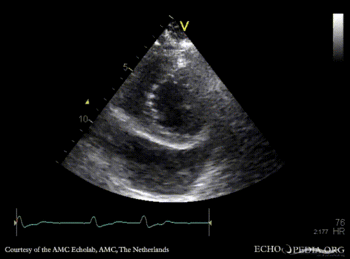

Continuous-wave Doppler signal of tricuspid regurgitation, pulmonary hypertension A4CH: dilated coronary sinus